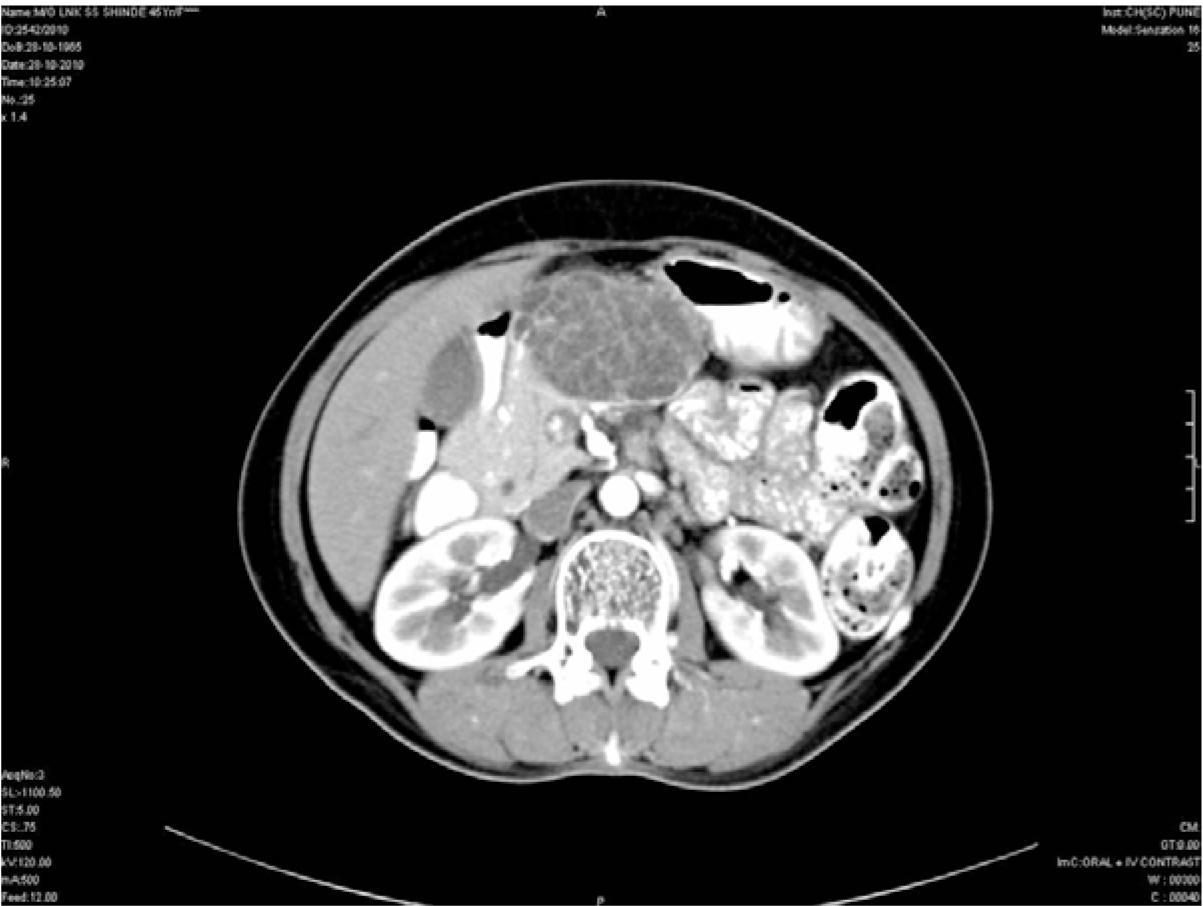

On admission to the hospital, chest and abdominal X-rays were performed which were inconclusive. Routine laboratory studies including hematological and biochemical parameters were normal. Serum amylase was within normal limits. Following this an ultrasound of the abdomen was performed. Ultrasound showed a well-delineated, multi-loculated, cystic lesion of size 5.2x6.2x7.7 cm in the body of the pancreas. The cysts were all subcentimetric giving a honeycomb appearance to the lesion. (Figure 1) Subsequently, a barium meal study was done which showed a smooth extrinsic indentation on the lesser curvature of the stomach. (Figure 2) Contrast-enhanced computed tomography scan showed a large, lobulated, well defined, lesion with multiple subcentimetric non enhancing hypodense cystic areas with enhancing hyperdense walls in the body of pancreas. (Figure 3) Multiple discrete foci of calcifications were seen within the lesion. (Figure 4) Anteriorly the lesion was reaching till anterior abdominal wall, posteriorly it was abutting the splenic vein, superiorly it was abutting the segment IV of liver and inferiorly it was abutting lesser curvature of stomach. After complete investigations, patient was diagnosed as a case of cystic tumor of pancreas and she was operated upon with resection of the lesion. Histology of resected pancreatic tissue revealed multicystic lesion in the body of pancreas containing cysts less than 1 cm in size lined by small flat to cuboidal cells. (Figure 5) There was no architectural or cytological atypia noted. Based on the imaging findings and further confirmation by histopathology a diagnosis of serous cystadenoma of pancreas was made.

Figure 3: Contrast enhanced computed tomography of the abdomen showing a multicystic structure with enhancing walls and septae in the body of pancreas.